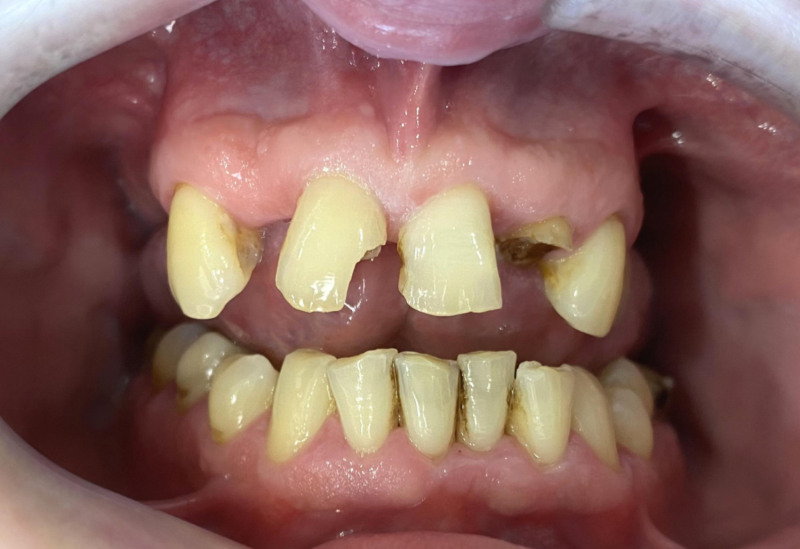

Wykonana praca protetyczna:

- most pełnołukowy na sześciu implantach

- korony na zęby własne w łuku dolnym

- korony na implantach w miejscach braków zębów

- odbudowa flow-injection zębów dolnych przednich